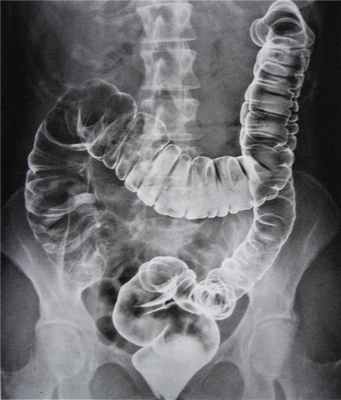

- контрастная клизма (ирригоскопия) — толстую кишку при помощи клизмы заполняют веществом (как правило, сульфатом бария), которое видно при рентгенологическом просвечивании. При этом хорошо видны неровности контуров кишки, ее сужения и другие симптомы;

Ведущее исследование выполняется методом колоноскопии для исключения органической патологии. Анализы крови, как правило, не выявляют изменений. Ирригоскопия применяется для исключения новообразований.

![Ирригоскопия]()